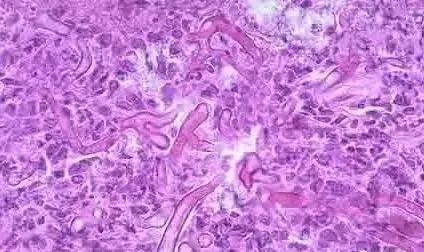

霉菌性阴道炎大多是由白色念珠菌(学名假丝酵母菌)感染引起的,因此霉菌性阴道炎也称为念珠菌性阴道炎,白色念珠菌作为常见菌群,它们在人体的皮肤、黏膜、消化道等多外都有寄生,但并不发病影响生活及工作,但是当遇到潮湿、闷热等适宜的环境时,念珠菌会大量繁殖侵袭人体,导致疾病的发生。所以在闷热的梅雨季节,很多女性都不约而同地发现,下身变得灼热瘙痒,甚至坐卧不宁,无法入睡,有时还尿频、尿痛,既痛苦又难堪——皆因她们的阴道在不知不觉间“发霉”了,即患上了俗称的霉菌性阴道炎。